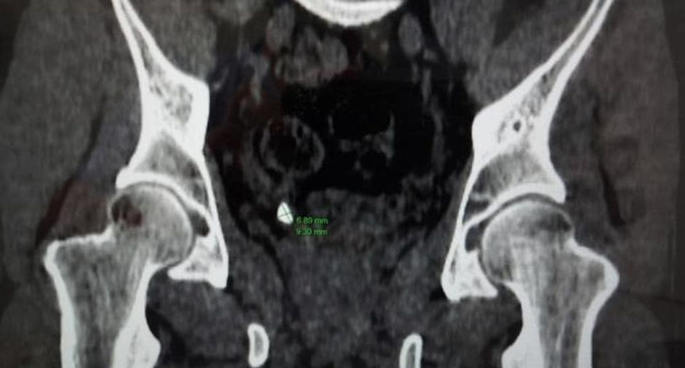

Sau khi thăm khám, các bác sĩ xác định người bệnh bị sỏi niệu quản phải 1/3 dưới xấp xỉ 9x7mm. Bất ngờ hơn, kết quả chụp CT các bác sĩ phát hiện người bệnh có thận niệu quản đôi hoàn toàn hai bên trái, phải và 2 niệu quản riêng biệt đều cắm xuống bàng quang.

Hình ảnh phim chụp CT khu phát hiện bất thường của bệnh nhân có 4 quả thận trong cơ thể